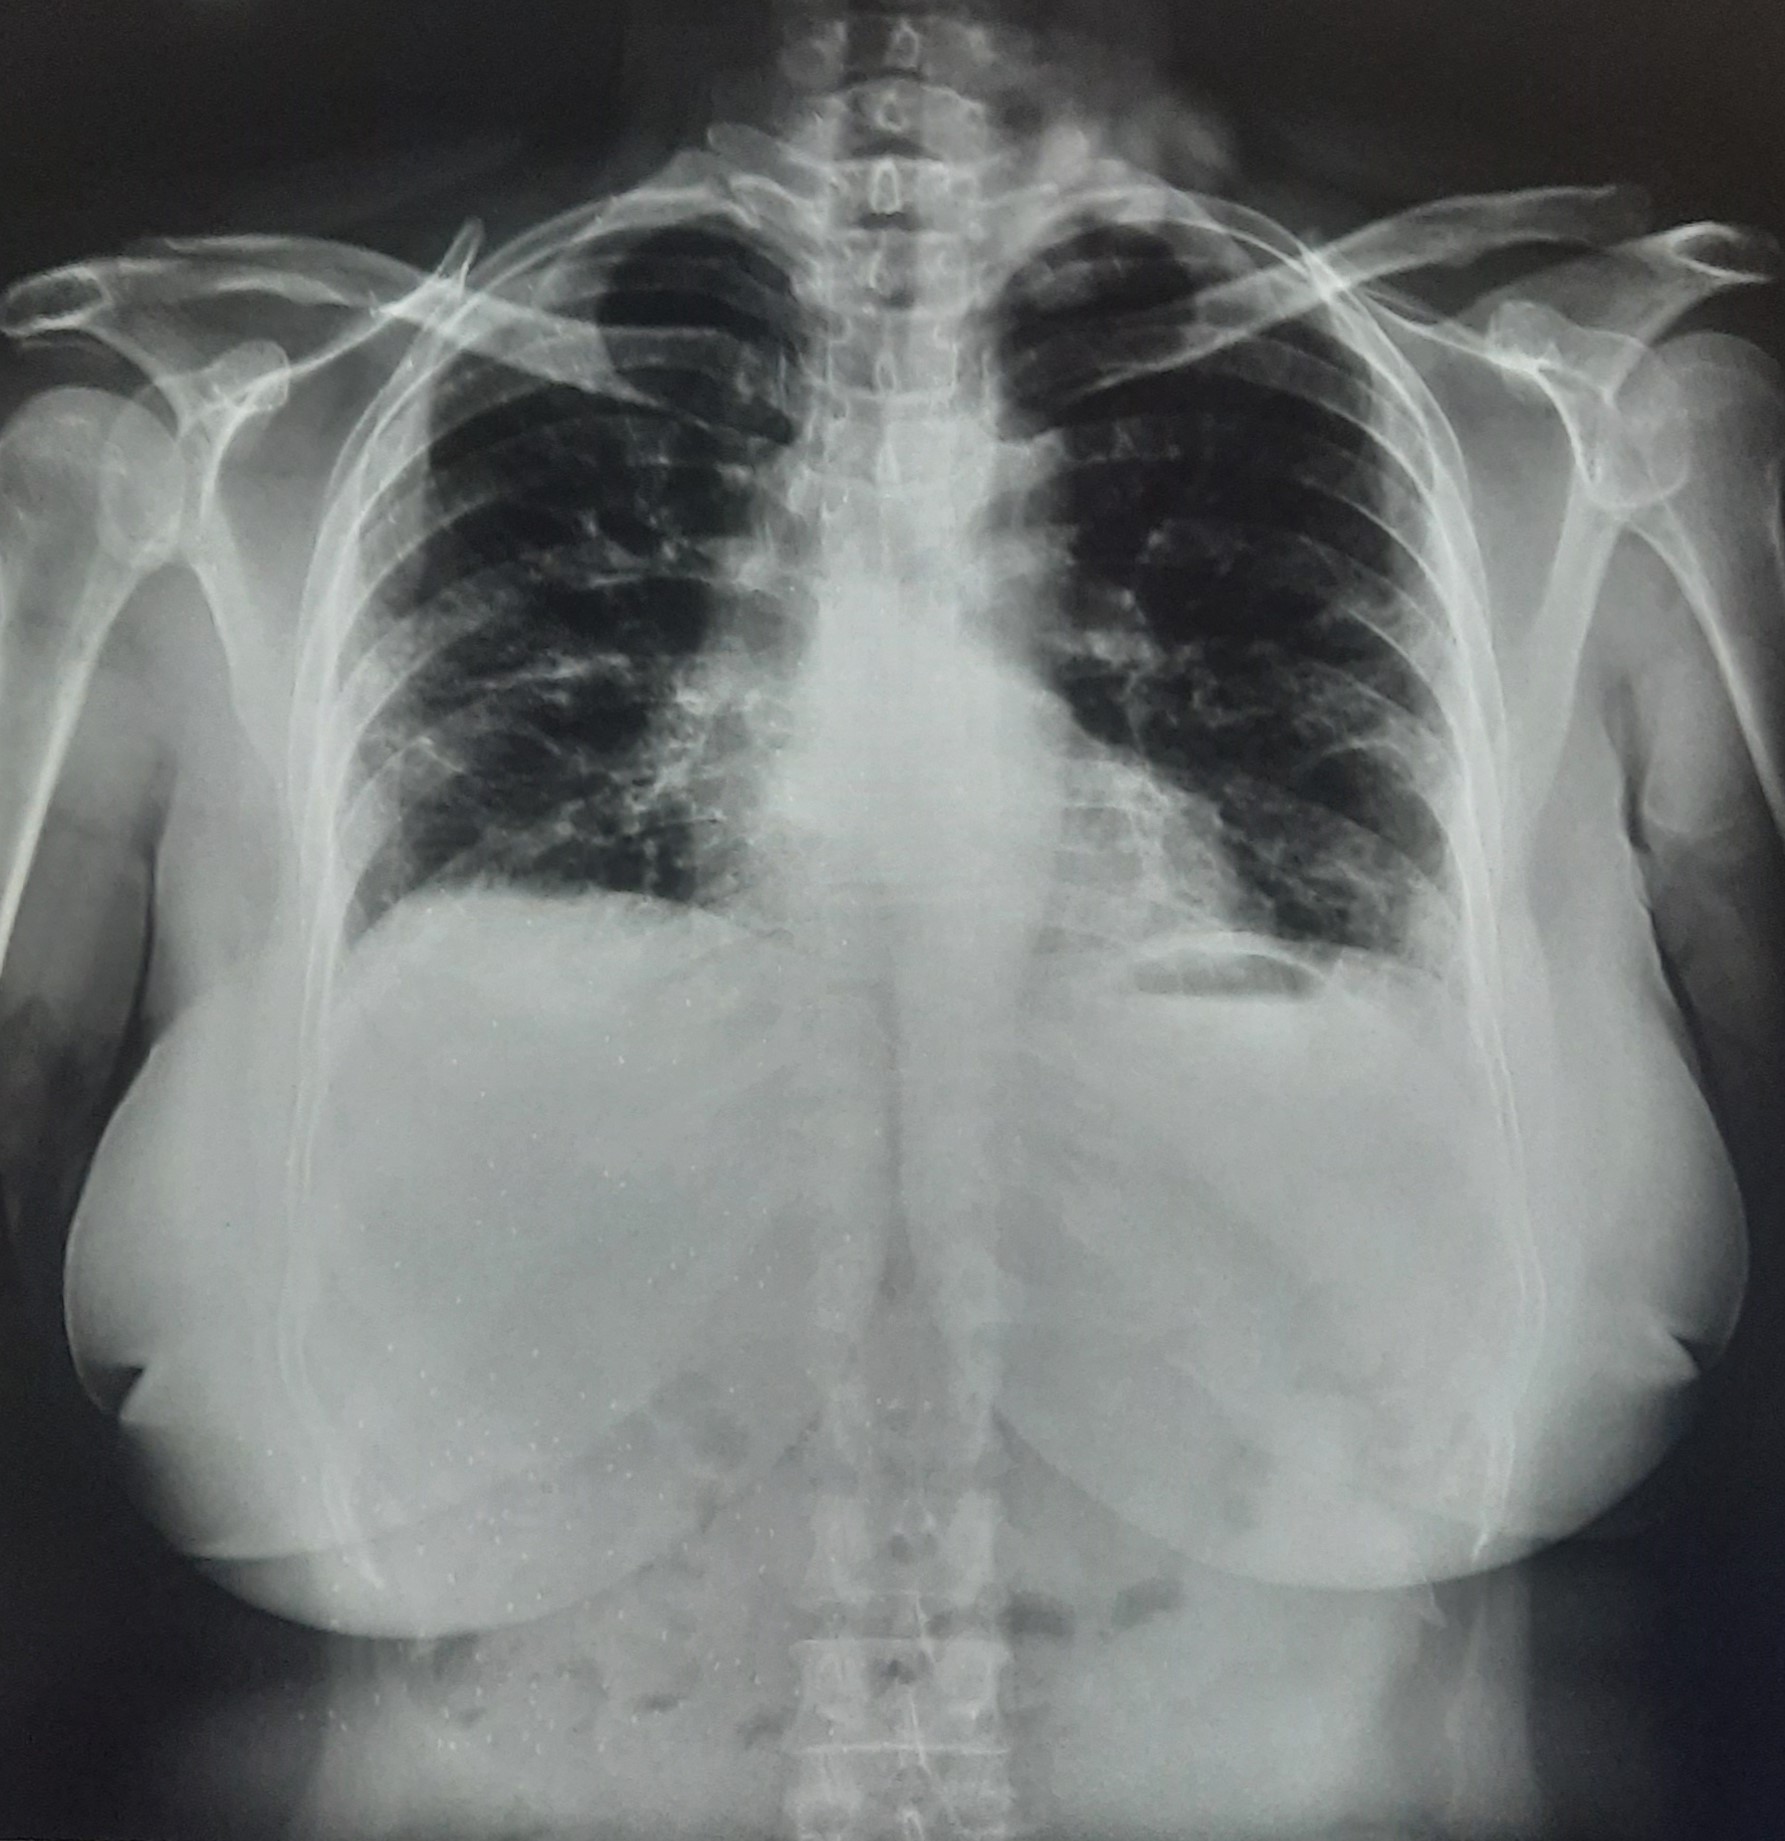

| 209 | IGGMC, Nagpur, Nagpur | P2 | 29-4263 | MONIKA KAITHAL | Consent taken on Paper | 47 Yrs. |

Provisional Diag : B/L LUNG CONSOLIDATION PNEUMONIA?

Final Diag : B/L CONSOLIDATION/PNEUMONIA |

TB Case (Confirmed) | B/L LUNG CONSOLIDATION | Abnormality visible on x-ray |

View |